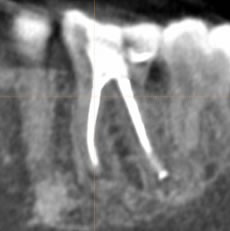

経過観察時のレントゲン写真

症状にもよりますが基本的には術後1ヶ月、3ヶ月、6ヶ月にレントゲン検査と歯の診査を行います。

被せ物の治療が可能と判断できたら、被せ物の治療に進んでいただきます。